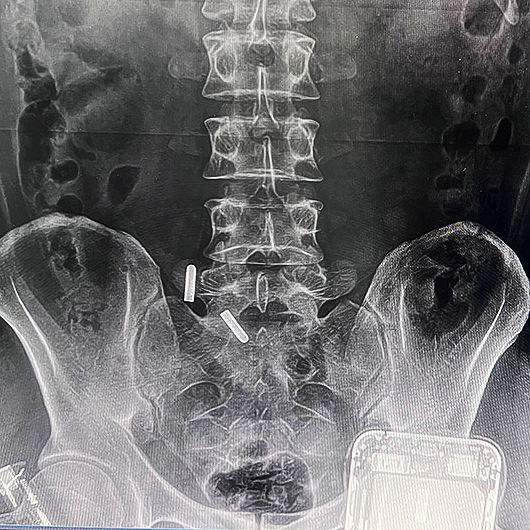

河北骨科诊所便携DR拍摄效果图

便携DR设备